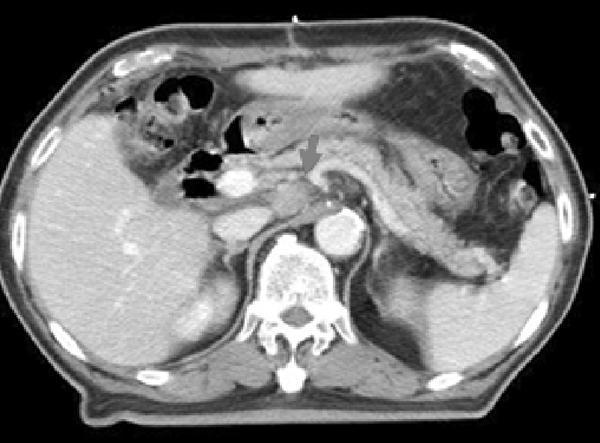

Unlikely to HBV reactivation, radiation-induced liver disease (RILD) is well-known complications after radiotherapy of the large volumes of liver. The underlying condition is venoocclusive disease of the small hepatic veins and characterized as anicteric elevation of ALP levels.10) Radiologically, an area of low attenuation is described, which was limited to the radiation portals for conventional doses more than 45 Gy.11) Focal radiation reaction is also observed without any clinical signs of RILD after conventional radiotherapy.12) Herfarth et al.13) reported radiological findings after stereotactic single dose radiotherapy of liver. Three reaction types were found on enhanced CT scans: type 1, hypodense portal-venous phase and isodense late phase, type 2, hypodense portal venous phase and hyperdense late phase, type 3, iso- or hyperdense portal-venous phase and hyperdense late phase. Type 1 and 2 reactions were observed significantly earlier than type 3 and reaction types shifted from type 1 to type 3 during follow-ups. The volume of the reaction also decreases during follow-up. Abnormal liver function test are usually considered as RILD in many cases of radiotherapy. In the HBV endemic areas, however, there are some possibilities of HBV reactivation after hepatic irradiation and some cases of previously considered fatal RILD might be caused by HBV reactivation or RILD combined with HBV reactivation.